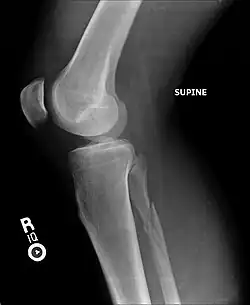

Ankle radiographs are used to detect widening of the tibiofibular syndesmosis or medial clear space. The medial clear space is the area between the talus of the ankle and the medial malleolus. Damage to the deltoid ligament and syndesmotic ligaments result in mortise instability, causing the talus to laterally shift and widen the medial clear space.[4][12] A clinical study, conducted in 2006 and published in the Journal of Bone and Joint Surgery, found that the medial clear space size of a normal ankle and an injured ankle measured at 4 millimetres and 5.4 millimetres in length respectively.[11] To confirm diagnosis, full-leg radiographs are used to inspect for fractures of the proximal fibula and widening of the interosseous clear space (or tibiofibular clear space). The interosseous clear space is the area between the medial side of the fibula and lateral side of the tibia. A peer-reviewed study, published in Injury in 2004, found that an interosseous clear space greater than 10 millimetres indicates diastasis of the syndesmotic ligaments.[4]